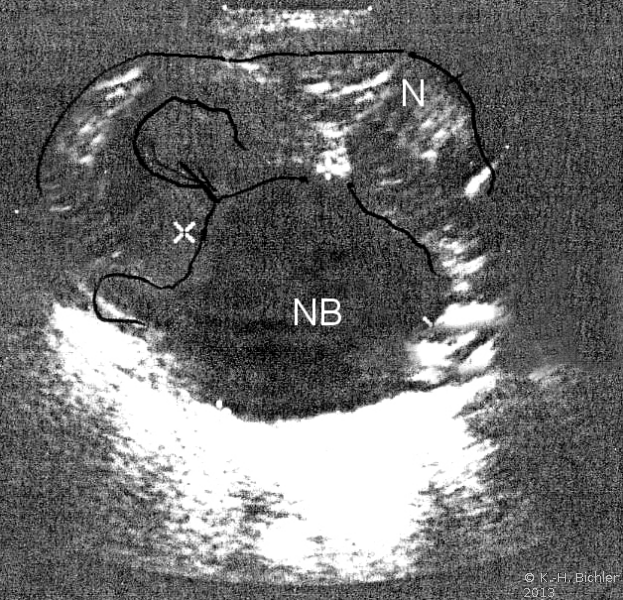

Sonographiebeispiele: Harnstau infolge Ureterabgangsstenosen (Abbildung 6a,b).